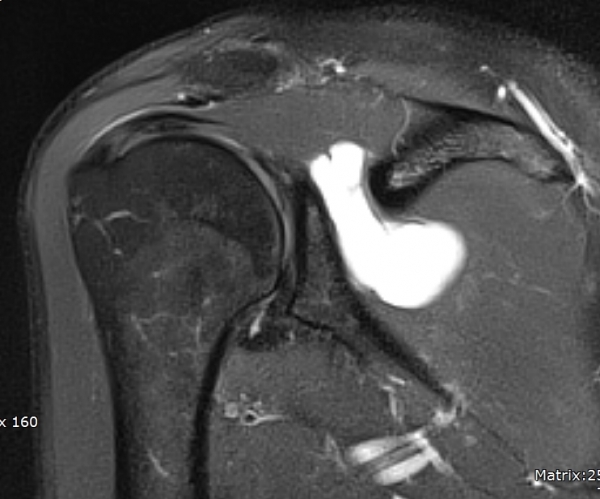

ÀÚ±â°ø¸í°Ë»ç

large paralabral cyst